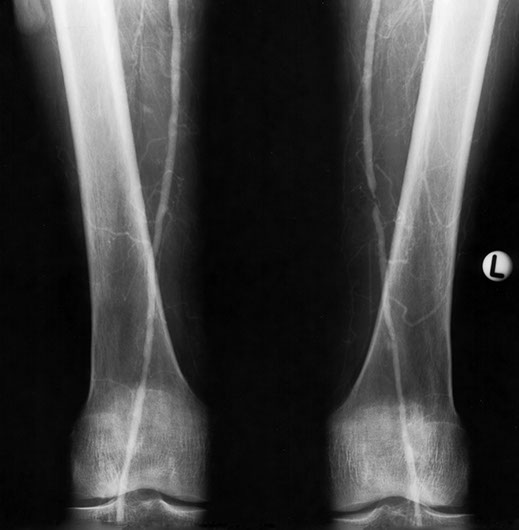

The most favourite subspecialty was angiography and interventional work particularly in the vascular field. This was the first angioplasty performed in the department. This represents atheroma with a focal stricture of the left femoral artery which was dilated with the presented result. Note that the atheromatous process is not limited to one area.

Femoral artery stricture post dilatation. Note the ragged appearance of the dilated atheromatous plaque.

This patient developed several strictures two years apart. This one is a popliteal stricture.

Popliteal stricture post dilatation

And this represents the second stricture two years later in the left lower femoral artery

And this is the post-dilatation image of the femoral stricture.

Thrombolysis can be performed on recently thrombosed sections due to embolic disease or focal narrowing by atheroma.

This is the image 8 hours post commencement of thrombolysis.